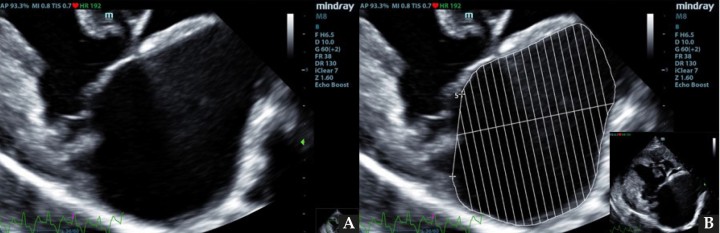

Se realizó la medición del volumen del atrio izquierdo con el método monoplano sumatorio de discos (MOD)[ Bouvard J, Thierry F, Culshaw GJ, et al. Assessment of left atrial volume in dogs: comparisons of two-dimensional and real-time three-dimensional echocardiography with ECG-gated multidetector computed tomography angiography. J Vet Cardiol 2019; 24: 64-77. [PubMed] ] a partir de la técnica de Simpson, que consiste en la medición del volumen del AI mediante la suma de los volúmenes de diferentes discos contiguos perpendiculares al eje mayor del AI generados por el software del ecógrafo, tras trazar el área del AI y su eje mayor de forma manual. Esta medición se realizó desde el corte paraesternal derecho longitudinal de 4 cámaras en telesístole, previo a la apertura de la válvula mitral (Fig. 1). Se siguió el borde endocárdico del atrio izquierdo, previo a la apertura de la válvula mitral en la telesístole cardíaca, sin incluir las venas pulmonares. Posteriormente, lo correlacionamos con el peso del paciente realizando la ratio: LAv/BW = volumen del atrio izquierdo (ml) / peso del paciente (kg).[ Höllmer M, Willesen JL, Tolver A, Koch J. Left atrial volume and function in dogs with naturally occurring myxomatous mitral valve disease. J Vet Cardiol 2017; 19(1): 24-34. [PubMed] , Höllmer M, Willesen JL, Tolver A, Koch J. Left atrial volume and phasic function in clinically healthy dogs of 12 different breeds. Vet J 2013; 197(3): 639-645. [PubMed] , Wesselowski S, Borgarelli M, Bello NM, Abbott J. Discrepancies in identification of left atrial enlargement using left atrial volume versus left atrial-to-aortic root ratio in dogs. J Vet Intern Med 2014; 28(5): 1527-1533. [PubMed] ]

ECDM. (A) Medida mediante MOD del volumen del AI. (B) Corte paraesternal derecho 4 cámaras, zoom AI. Ratio LA/BW = 3, 8 ml/kg.